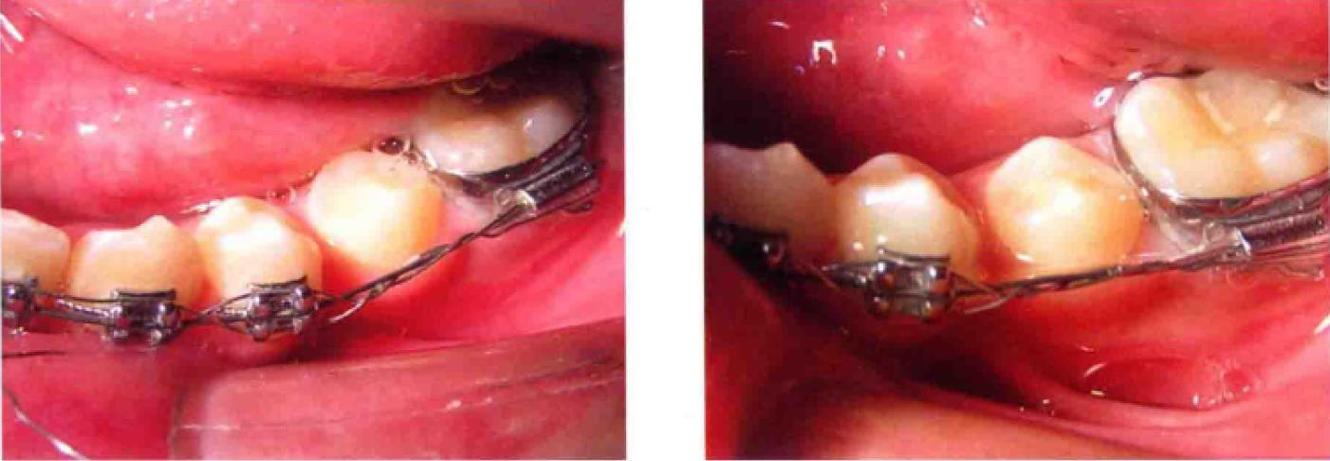

正畸结扎丝是直径0.15-0.25mm的金属丝(多为不锈钢或镍钛合金),通过缠绕、固定托槽翼,将弓丝稳定于托槽槽沟内,传递矫治力并维持牙齿位置,传统单丝结扎是将结扎丝直接绕过托槽与弓丝拧紧,而对折结扎则先将结扎丝对折成双股,再以双股形式进行结扎,相当于将结扎丝直径增加一倍,强度和稳定性显著提升。

对折结扎的核心在于“双股结构”,这种结构不仅增强了结扎丝的抗形变能力,还能减少单股结扎时可能出现的“滑脱”或“松动”,尤其适用于需要强支抗、复杂移动或口腔环境复杂的病例。

- 将对折后的双股结扎丝跨过托槽顶部,双股分置于托槽近远中两侧翼下方;

- 用持针器夹住双股末端,沿托槽翼内侧向弓丝方向缠绕,先绕近中翼,再绕远中翼(或交替缠绕),确保结扎丝紧贴托槽槽沟;

- 拧紧结扎丝时力度需适中:过松会导致托槽-弓丝相对移位,影响牙齿移动;过紧可能造成牙根吸收或疼痛,一般以结扎丝与弓丝轻微嵌合、无晃动为宜,可用结扎钳辅助拧2-3圈,末端剪断后用持针器将尾部压平,避免刺伤口腔软组织。